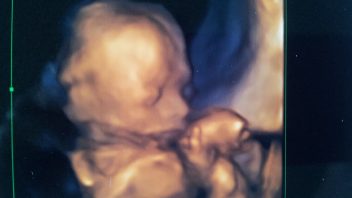

Zuzana se v 18. týdnu těhotenství. Co se děje s jejím tělem?